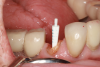

(5.) Prepared tooth with an oval shaped access before and after insertion of an oval-shaped post.

Figure 5

For oval-shaped canals, posts with an oval-shaped coronal two-thirds and a tapered, round apical one-third have been introduced. The oval-shaped section reduces the amount of coronal space that needs to be filled in and increases the flexural strength of the post in that region (Figure 5). These posts are useful adjuncts, providing better adaptation13 and increased fracture resistance.14 Similar to other available systems, oval-shaped post systems require separate, specific instruments to accommodate and fit the various sizes.